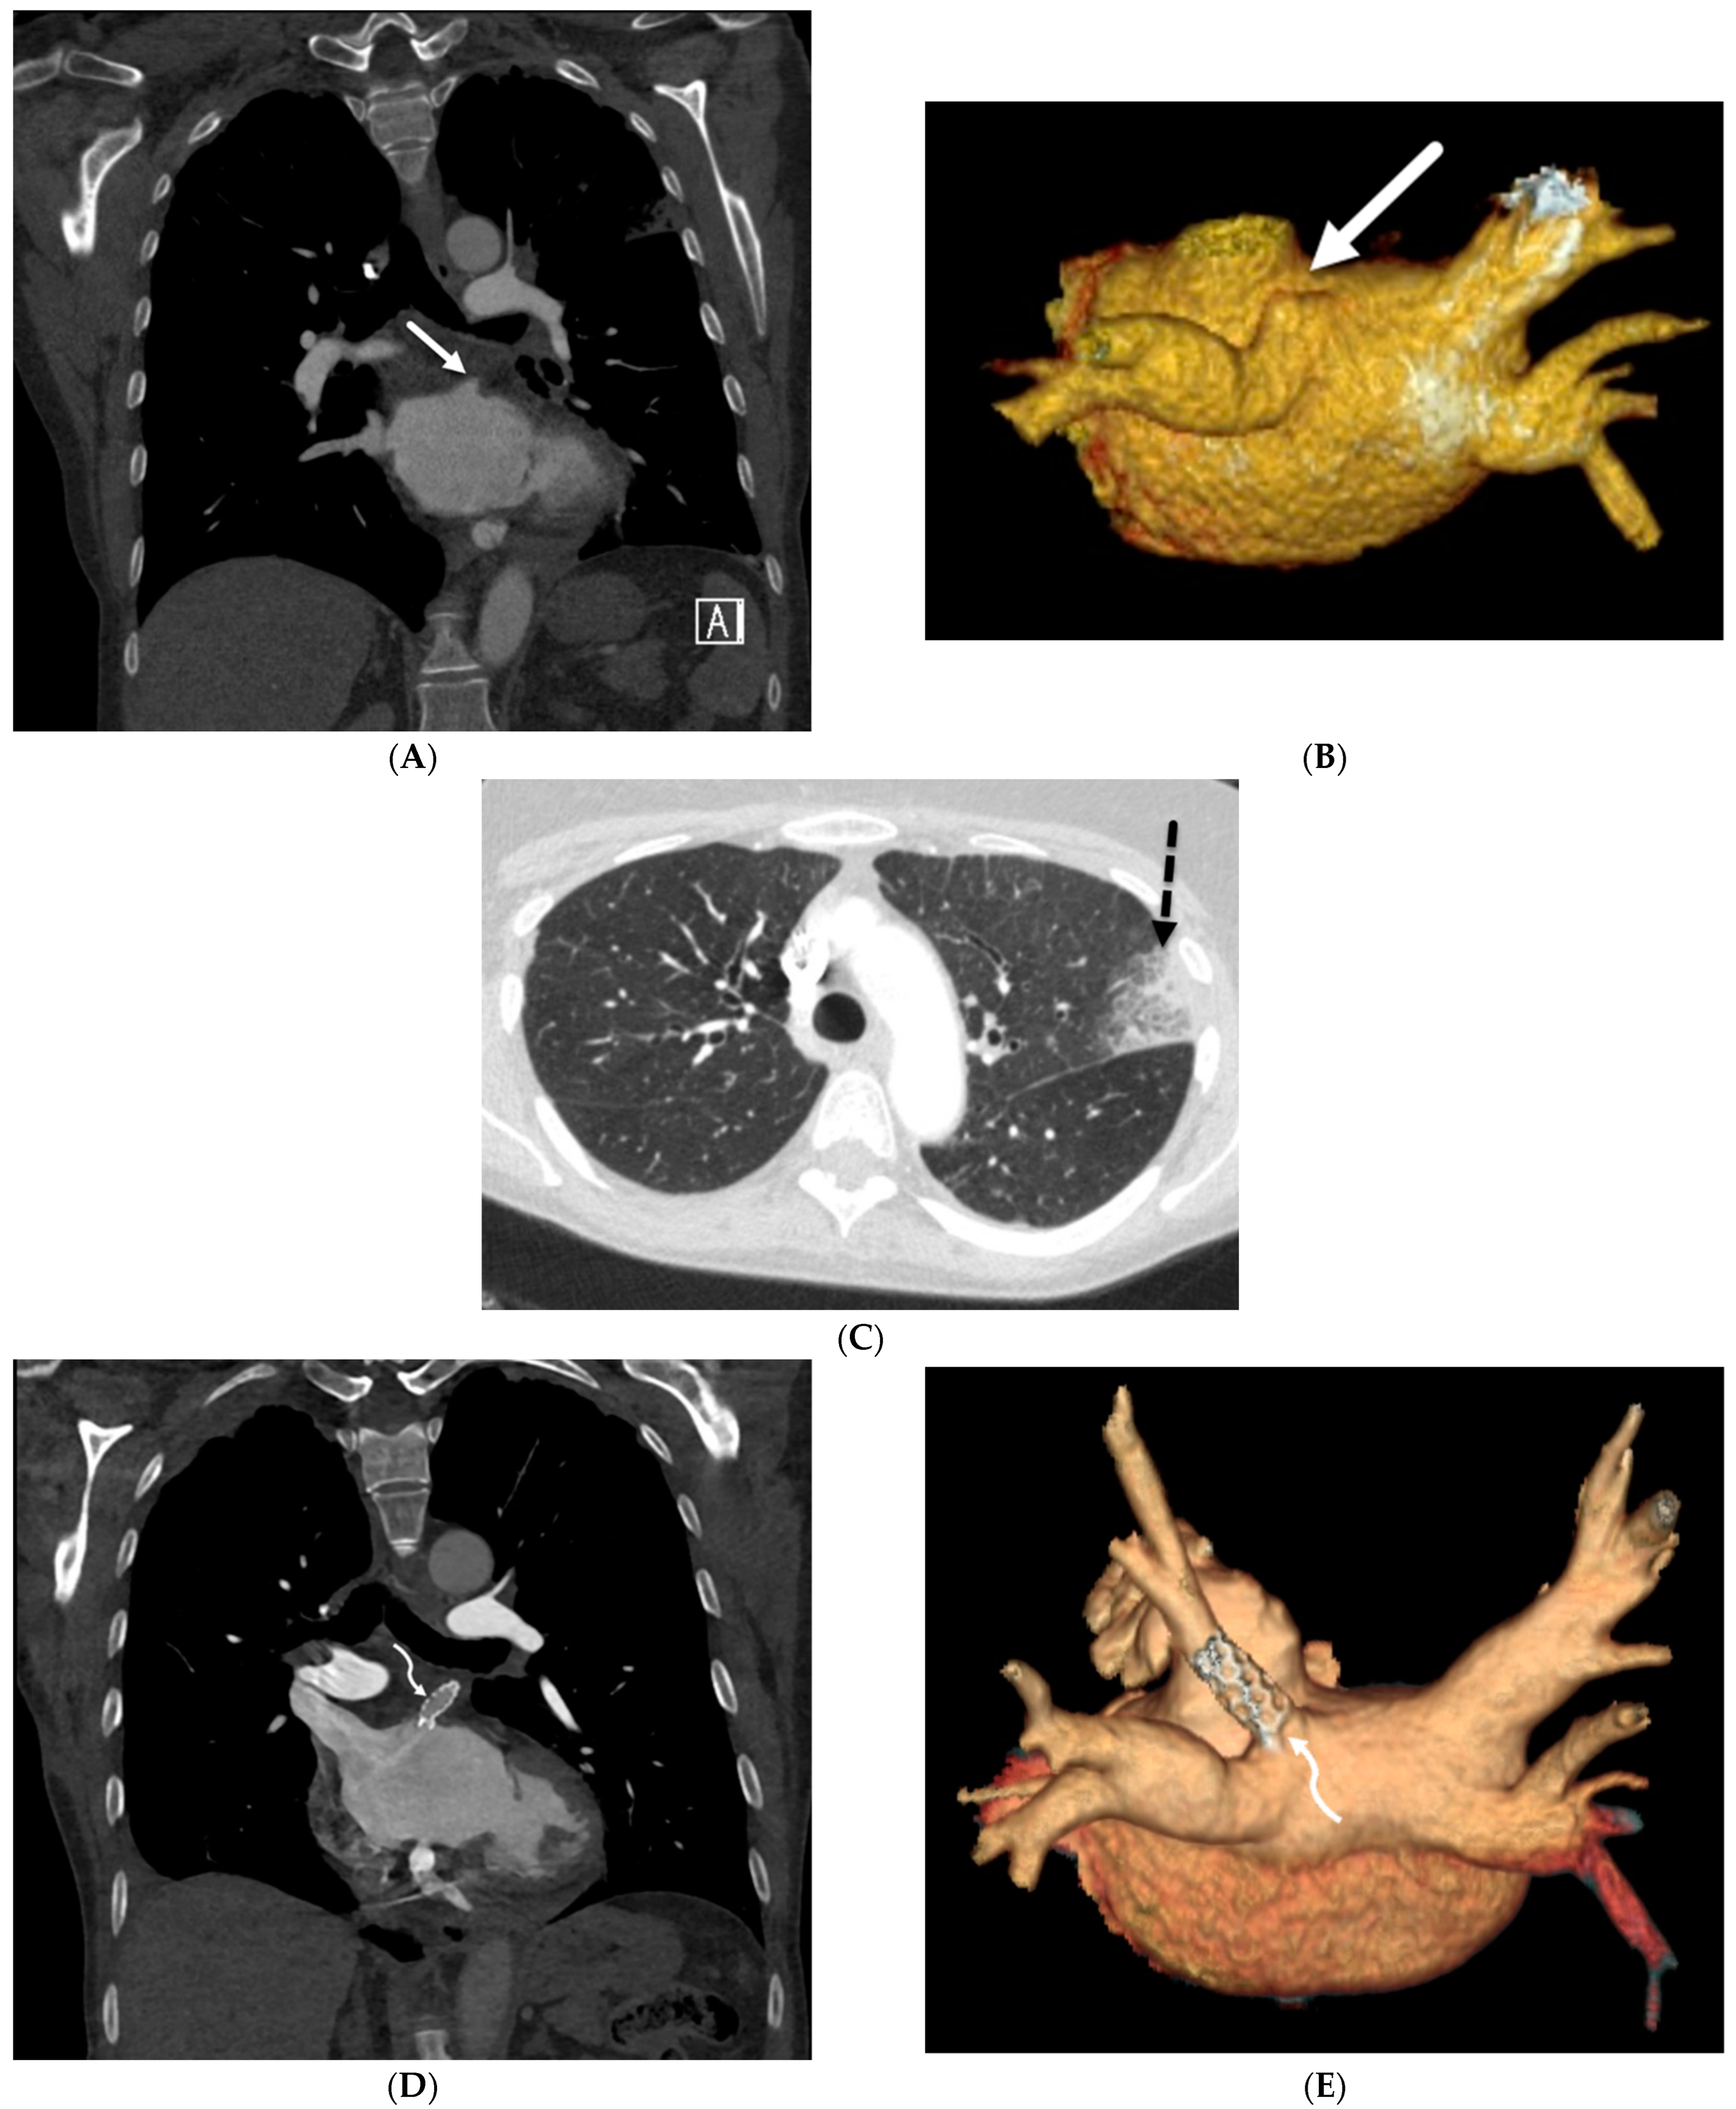

Smooth![]() | Infectious: Viral pneumonia including COVID-19 pneumonia, Pneumocystis jiroveci pneumonia (PJP) Miscellaneous: Pulmonary edema, pulmonary hemorrhage Inherited: Yellow nail syndrome (YNS), pulmonary capillary hemangiomatosis (PCH), pulmonary veno-occlusive disease (PVOD), pulmonary lymphangiomatosis, coatomer subunit alpha (COPA) syndrome Depositional: Pulmonary alveolar proteinosis (PAP) Iatrogenic: Drug toxicity, radiation pneumonitis, lipoid pneumonia, e-cigarette or vaping use-associated lung injury (EVALI) Granulomatous: Erdheim Chester disease (ECD) |

Nodular![]() | Neoplasia: Leukemia, lymphoma, Kaposi’s sarcoma, lymphangitic carcinomatosis Interstitial lung diseases: Nonspecific interstitial pneumonia (NSIP), usual interstitial pneumonia (UIP), lymphoid interstitial pneumonia (LIP) Exposures: Silicosis, coal worker’s pneumoconiosis (CWP), asbestosis Inherited: Chronic granulomatous disease, Niemann–Pick disease Depositional: Amyloidosis Iatrogenic: Silicone embolization Granulomatous diseases: Sarcoidosis Infiltrative: IgG4-related lung disease (RLD) |

Irregular![]() | Granulomatous diseases: Sarcoidosis Interstitial lung diseases: Usual interstitial pneumonia (UIP) Inhalational: Asbestosis |